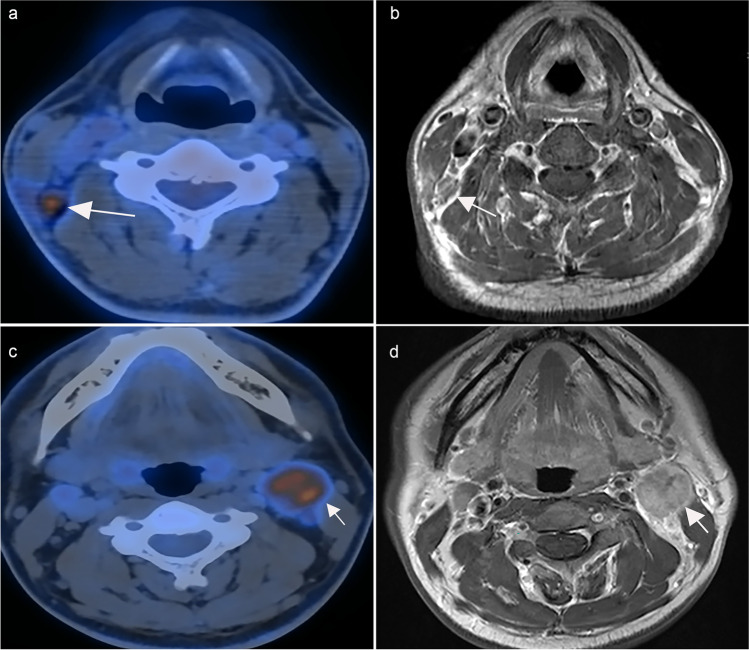

The PET/CT and MRI protocols are described in the Supplementary Methods. MRI images were read by two experienced radiologists, and PET/CT was read by two experienced nuclear physicians who were blinded to the MRI results. Any differences were resolved by consensus. Metastatic lymph nodes were diagnosed according to the radiologic criteria [11]: (1) retropharyngeal lymph nodes with a minimal axial diameter of 5 mm or greater and cervical lymph nodes with a minimal axial diameter of 10 mm or greater; (2) minimal axial diameter of 8 mm for clusters of 3 or more lymph nodes; and (3) lymph nodes with necrosis or extranodal extension. Similar to a previous study [12], radiologic extranodal extension was categorized into 4 grades: grade 0, no extranodal extension; grade 1, invasion to surrounding fat; grade 2, coalescent nodes; grade 3, infiltrating adjacent structures. As reported [13], the diagnostic criteria for nodal necrosis based on MRI included (1) focal area of low signal intensity on T1-weighted images with or without enhanced edges and (2) focal area of high signal intensity on T2-weighted images. On PET/CT, lymph nodes were considered positive when [18F]-FDG uptake increased significantly compared with the background [14]. In the final decision-making, the PET/CT results were supplemented with the MRI findings (Fig. 1).

Fig. 1.

Cervical lymph nodes in PET/CT (left) and contrast-enhanced T1-weighted MRI (right), a PET/CT correctly diagnosed positive lymph nodes, while MRI diagnosed negative lymph nodes by mistake (b); both PET/CT (c) and MRI (d) correctly detected metastatic lymph nodes. Abbreviations: MRI, magnetic resonance imaging; PET/CT, [18F]-fluorodeoxyglucose positron emission tomography with computed tomography